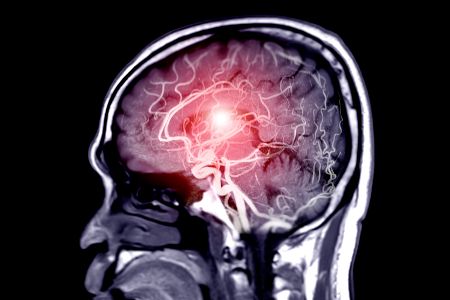

Bei Migräne werden Proteine im Hirnwasser freigesetzt, die die Blut-Hirn-Schranke überwinden und Nervenzellen im Ganglion trigeminale reizen.

Der Ganglion trigeminale ist ein empfindlicher Knotenpunkt an der Schädelbasis, der das Gehirn mit Gesicht und Kopf verbindet.

Diese Proteine aktivieren Schmerzrezeptoren und verursachen Kopfschmerzen und Wahrnehmungsstörungen.

Der Mechanismus ist seitengetrennt: Proteine binden auf derselben Kopfhälfte, was einseitige Schmerzen erklärt.

Gehirnscans bestätigen diesen Mechanismus auch bei Menschen, was neue Medikamente ermöglichen könnte.